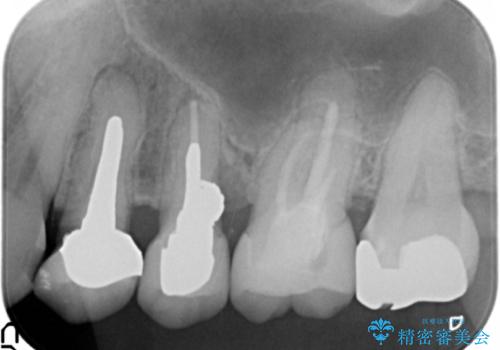

- 違和感や疼きのある左側小臼歯に加え全体的にクラウンや詰め物のやりかえを希望され来院されました。

治療後に再発した虫歯や根管再治療に加え、穴の空き症状のある上顎左側小臼歯は抜去を行いインプラントによる機能回復治療を計画します。

X線写真検査ではわからない虫歯も外してみると再発していることがあります。虫歯を丁寧に取り除き、再発を防ぐべく精密なクラウンの作製を行うことが長期的な予後につながります。